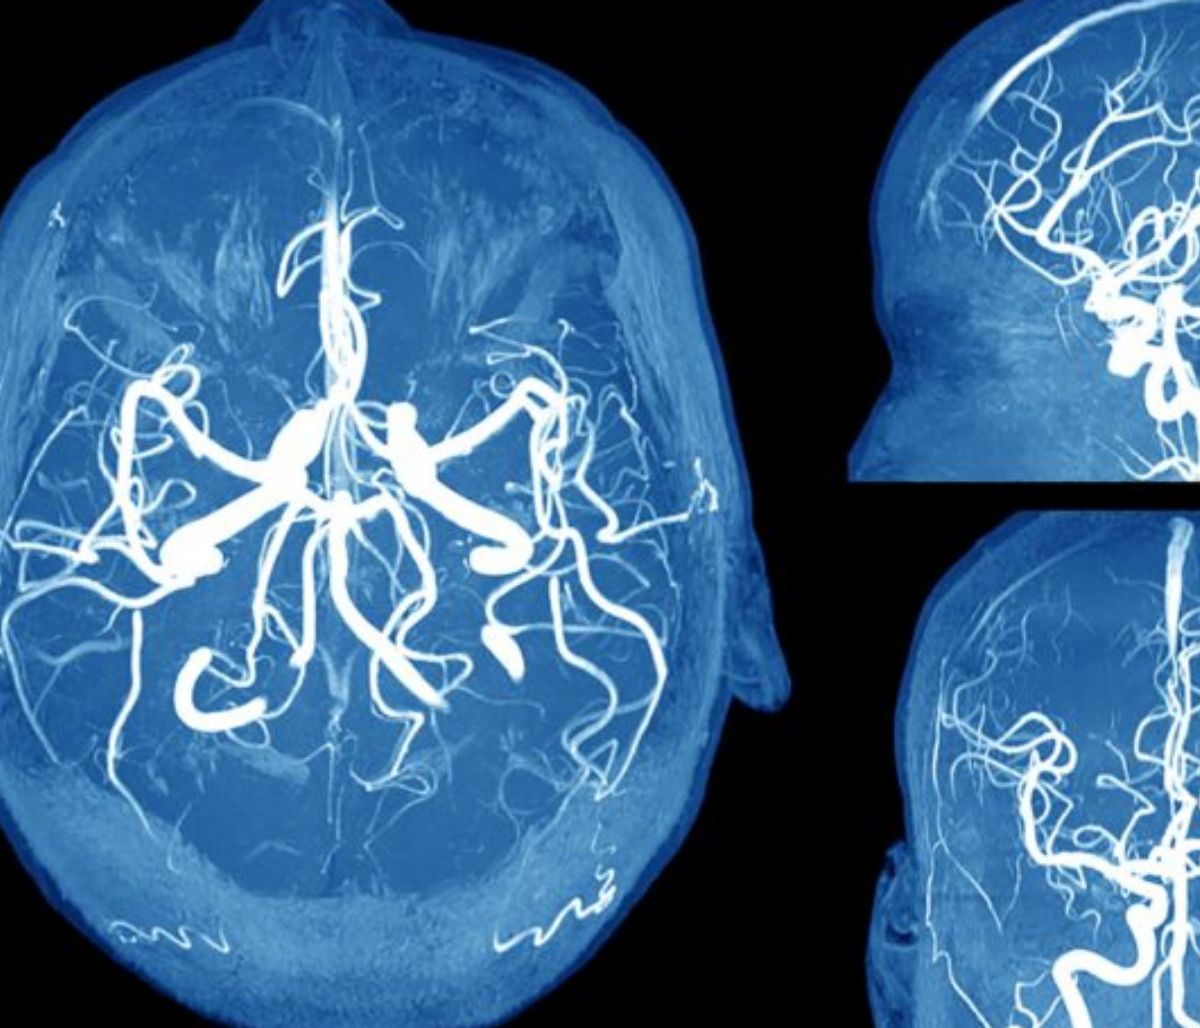

Ανεύρυσμα εγκεφάλου: Τα συμπτώματα SOS που πρέπει να γνωρίζετε (φωτο)

Το ανεύρυσμα εγκεφάλου είναι η διόγκωση ενός αιμοφόρου αγγείου στον εγκέφαλο, σύμφωνα με την κλινική Mayo.